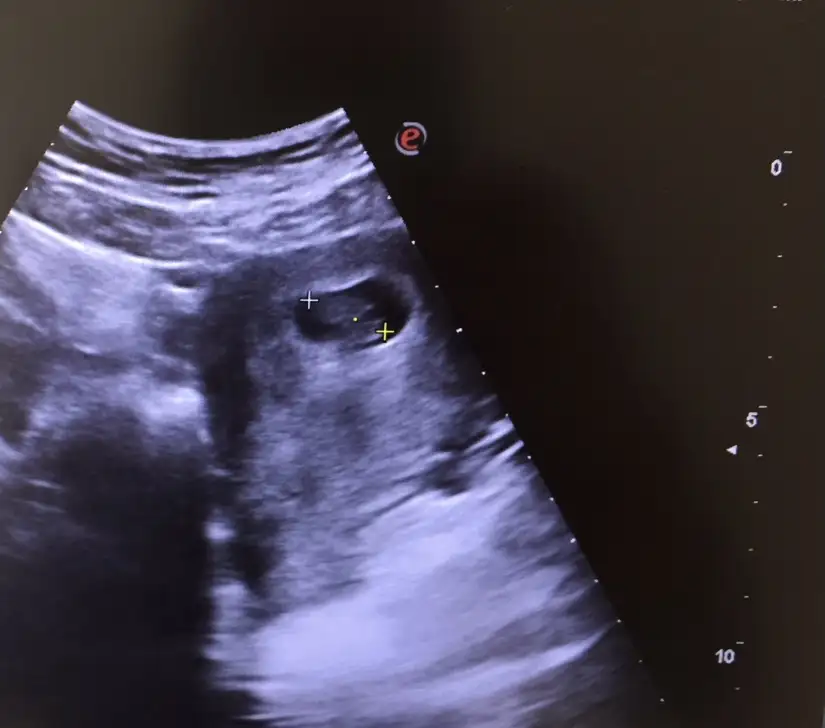

Bende böyle bir şey okurmuştum bazı sayfalarda 9+4 ü 9 haftalık almış bazıları 10 haftalık 10 haftalığa baktıysan büyük görmüşündür. Bende şuan 9+4 üm 28 mm dedi gayet normal

Ay rahatladım teşekkür ederim, uygulamada da yaklaşık 4 cm diyince korktum. Size iyi dedi dimi doktorunuz